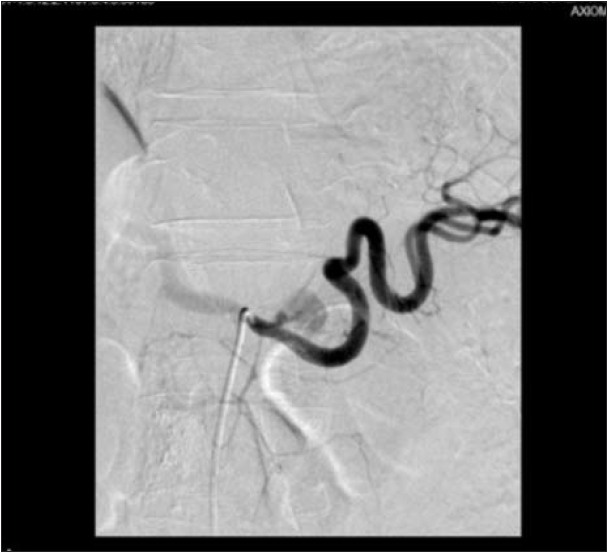

Although the initial postoperative course was uneventful, during the 4th postoperative (p.o.) day the patient presented repeated melenic

stools. We decided to perform a selective celiac trunk angiography with the suspicion of a bleeding from the WON. After catheterization of the celiac trunk the contrast injection revealed a brief and small extravasation of contrast, that did not reappear after repeated injections of contrast agent for a period of as long as at least 40 minutes. As the origin of the bleeding was not properly located and no other bleeding was identified we decided to put the patient under close observation in the surgical ward (Figs. 2,3). The patient displayed a good general status, with no melenic stools and a hemodynamically stable condition, still he received multiple blood transfusions as hemoglobin level was below 8 g/dl.